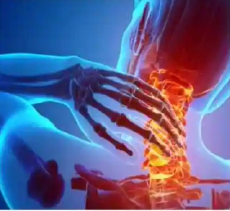

ImariMed Rehabilitation Center is a world leader in advanced rehabilitation treatment and research – serving the greater Middle East and Africa region and beyond, our leading medical products, professionals, clinicians and researchers will help you through your most challenging journey, so you can be the best version of yourself. Combining your unstoppable spirit with our resources. That’s the power of hope. Let’s do amazing things together.

Your best protection is knowledge, management and prevention